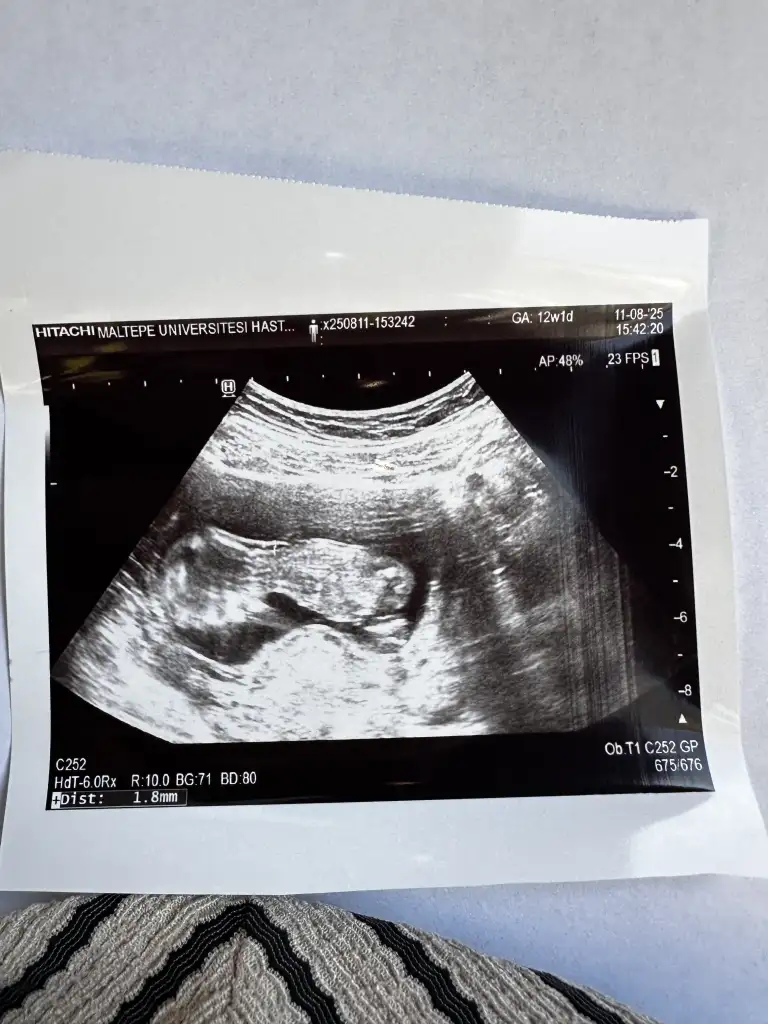

Benim nedir sizce 11+1Erkek bence

Bu bebis de erkek gibi geldi bana ama bilemedim yine de :))Benim nedir sizce 11+1

Ay benimde 12 +1 bana da tahminde bulunabilir misinizKız gördüm sanki, sağlıcakla gelsin

Yüz üstü durmuş sankiAy benimde 12 +1 bana da tahminde bulunabilir misiniz![]()

Evet yüz üstü yatıyor o yüzden doktorda bişey diyemedi belki sizin bi tahmininiz vardır diye sormak istedimYüz üstü durmuş sanki![]()